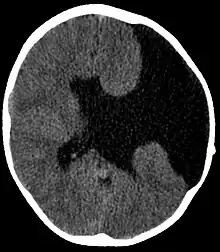

| Axial CT scan showing schizencephaly in a 6-year-old child | |

Schizencephaly (from Greek skhizein 'to split', and enkephalos 'brain')[1][2] is a rare birth defect characterized by abnormal clefts lined with grey matter that form the ependyma of the cerebral ventricles to the pia mater. These clefts can occur bilaterally or unilaterally. Common clinical features of this malformation include epilepsy, motor deficits, and psychomotor retardation.[3]